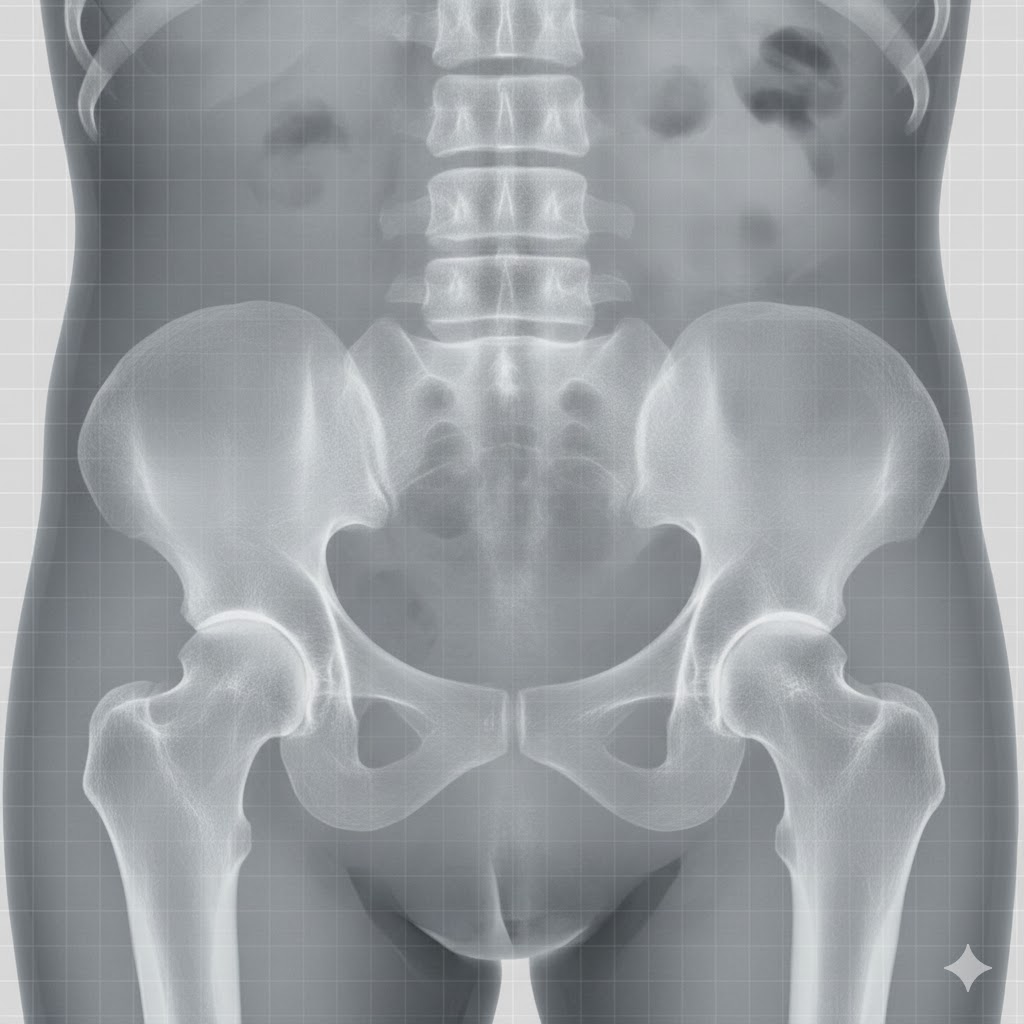

- تعویض مفصل لگن در موارد شدید و پیشرفته آرتروز لگن

- تشخیص و درمان دررفتگی مادرزادی لگن